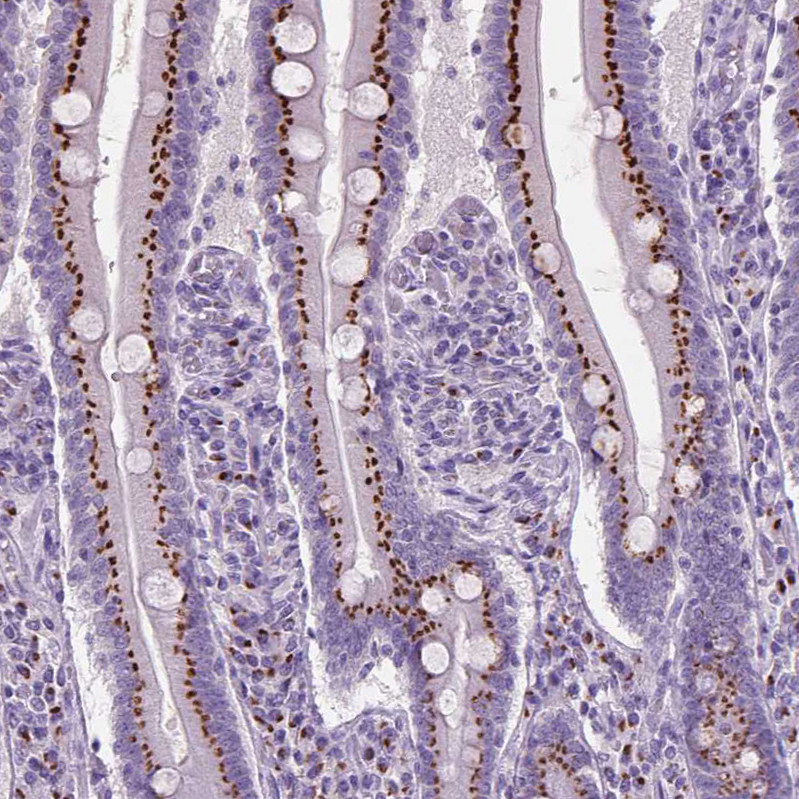

Immunohistochemistry analysis in human small intestine and skeletal muscle tissues using HPA064001 antibody. Corresponding SLC35C1 RNA-seq data are presented for the same tissues.